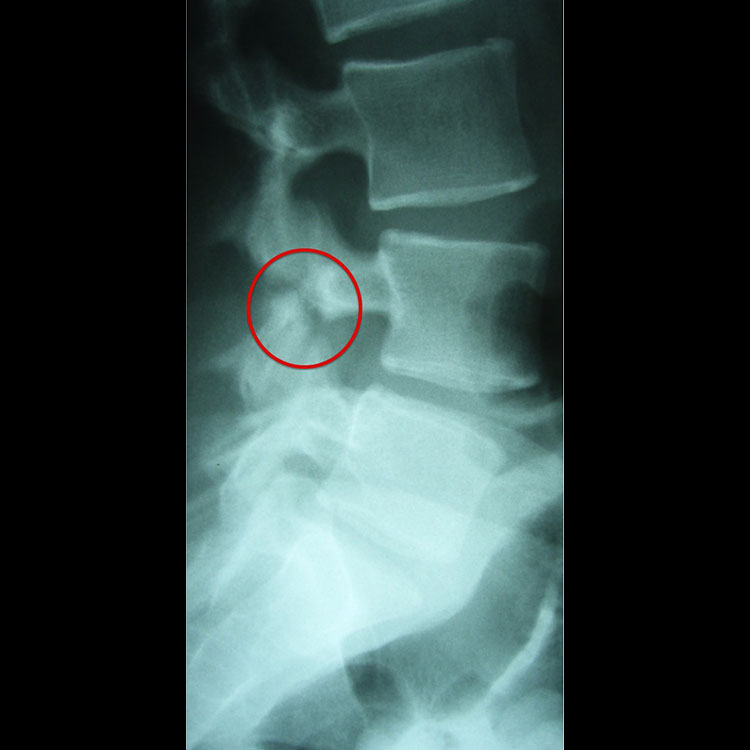

척추분리증 (Spondylolysis): 비수술적 관리가 일반적이지만, 세부 사항은 다양합니다. 모든 스포츠 및 악화 활동으로부터 통증이 상대적으로 없어질 때까지 휴식 기간이 필요합니다. 증상이 완화되면 동적 코어 안정성 및 유연성 개선을 위한 4~6주 재활 프로그램이 시작됩니다.